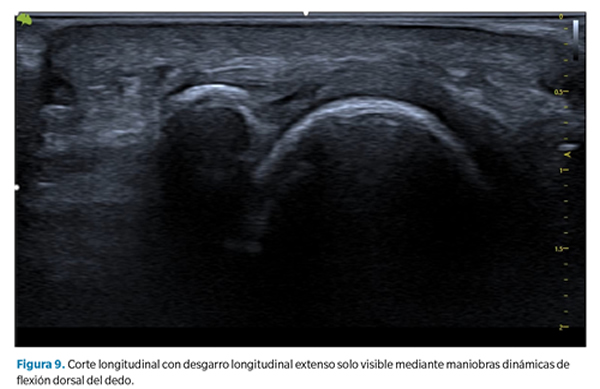

2. Aplanamiento y atenuación de la placa plantar. En estos casos no se observa un defecto de forma tan clara, pero debe llamarnos la atención cuando la zona de inserción, generalmente más gruesa, se aprecia más adelgazada que la zona media o proximal de la placa. Esto sugiere generalmente la presencia de un desgarro transversal que abarca desde la porción lateral hasta la porción central de la placa40 (Figura 9).